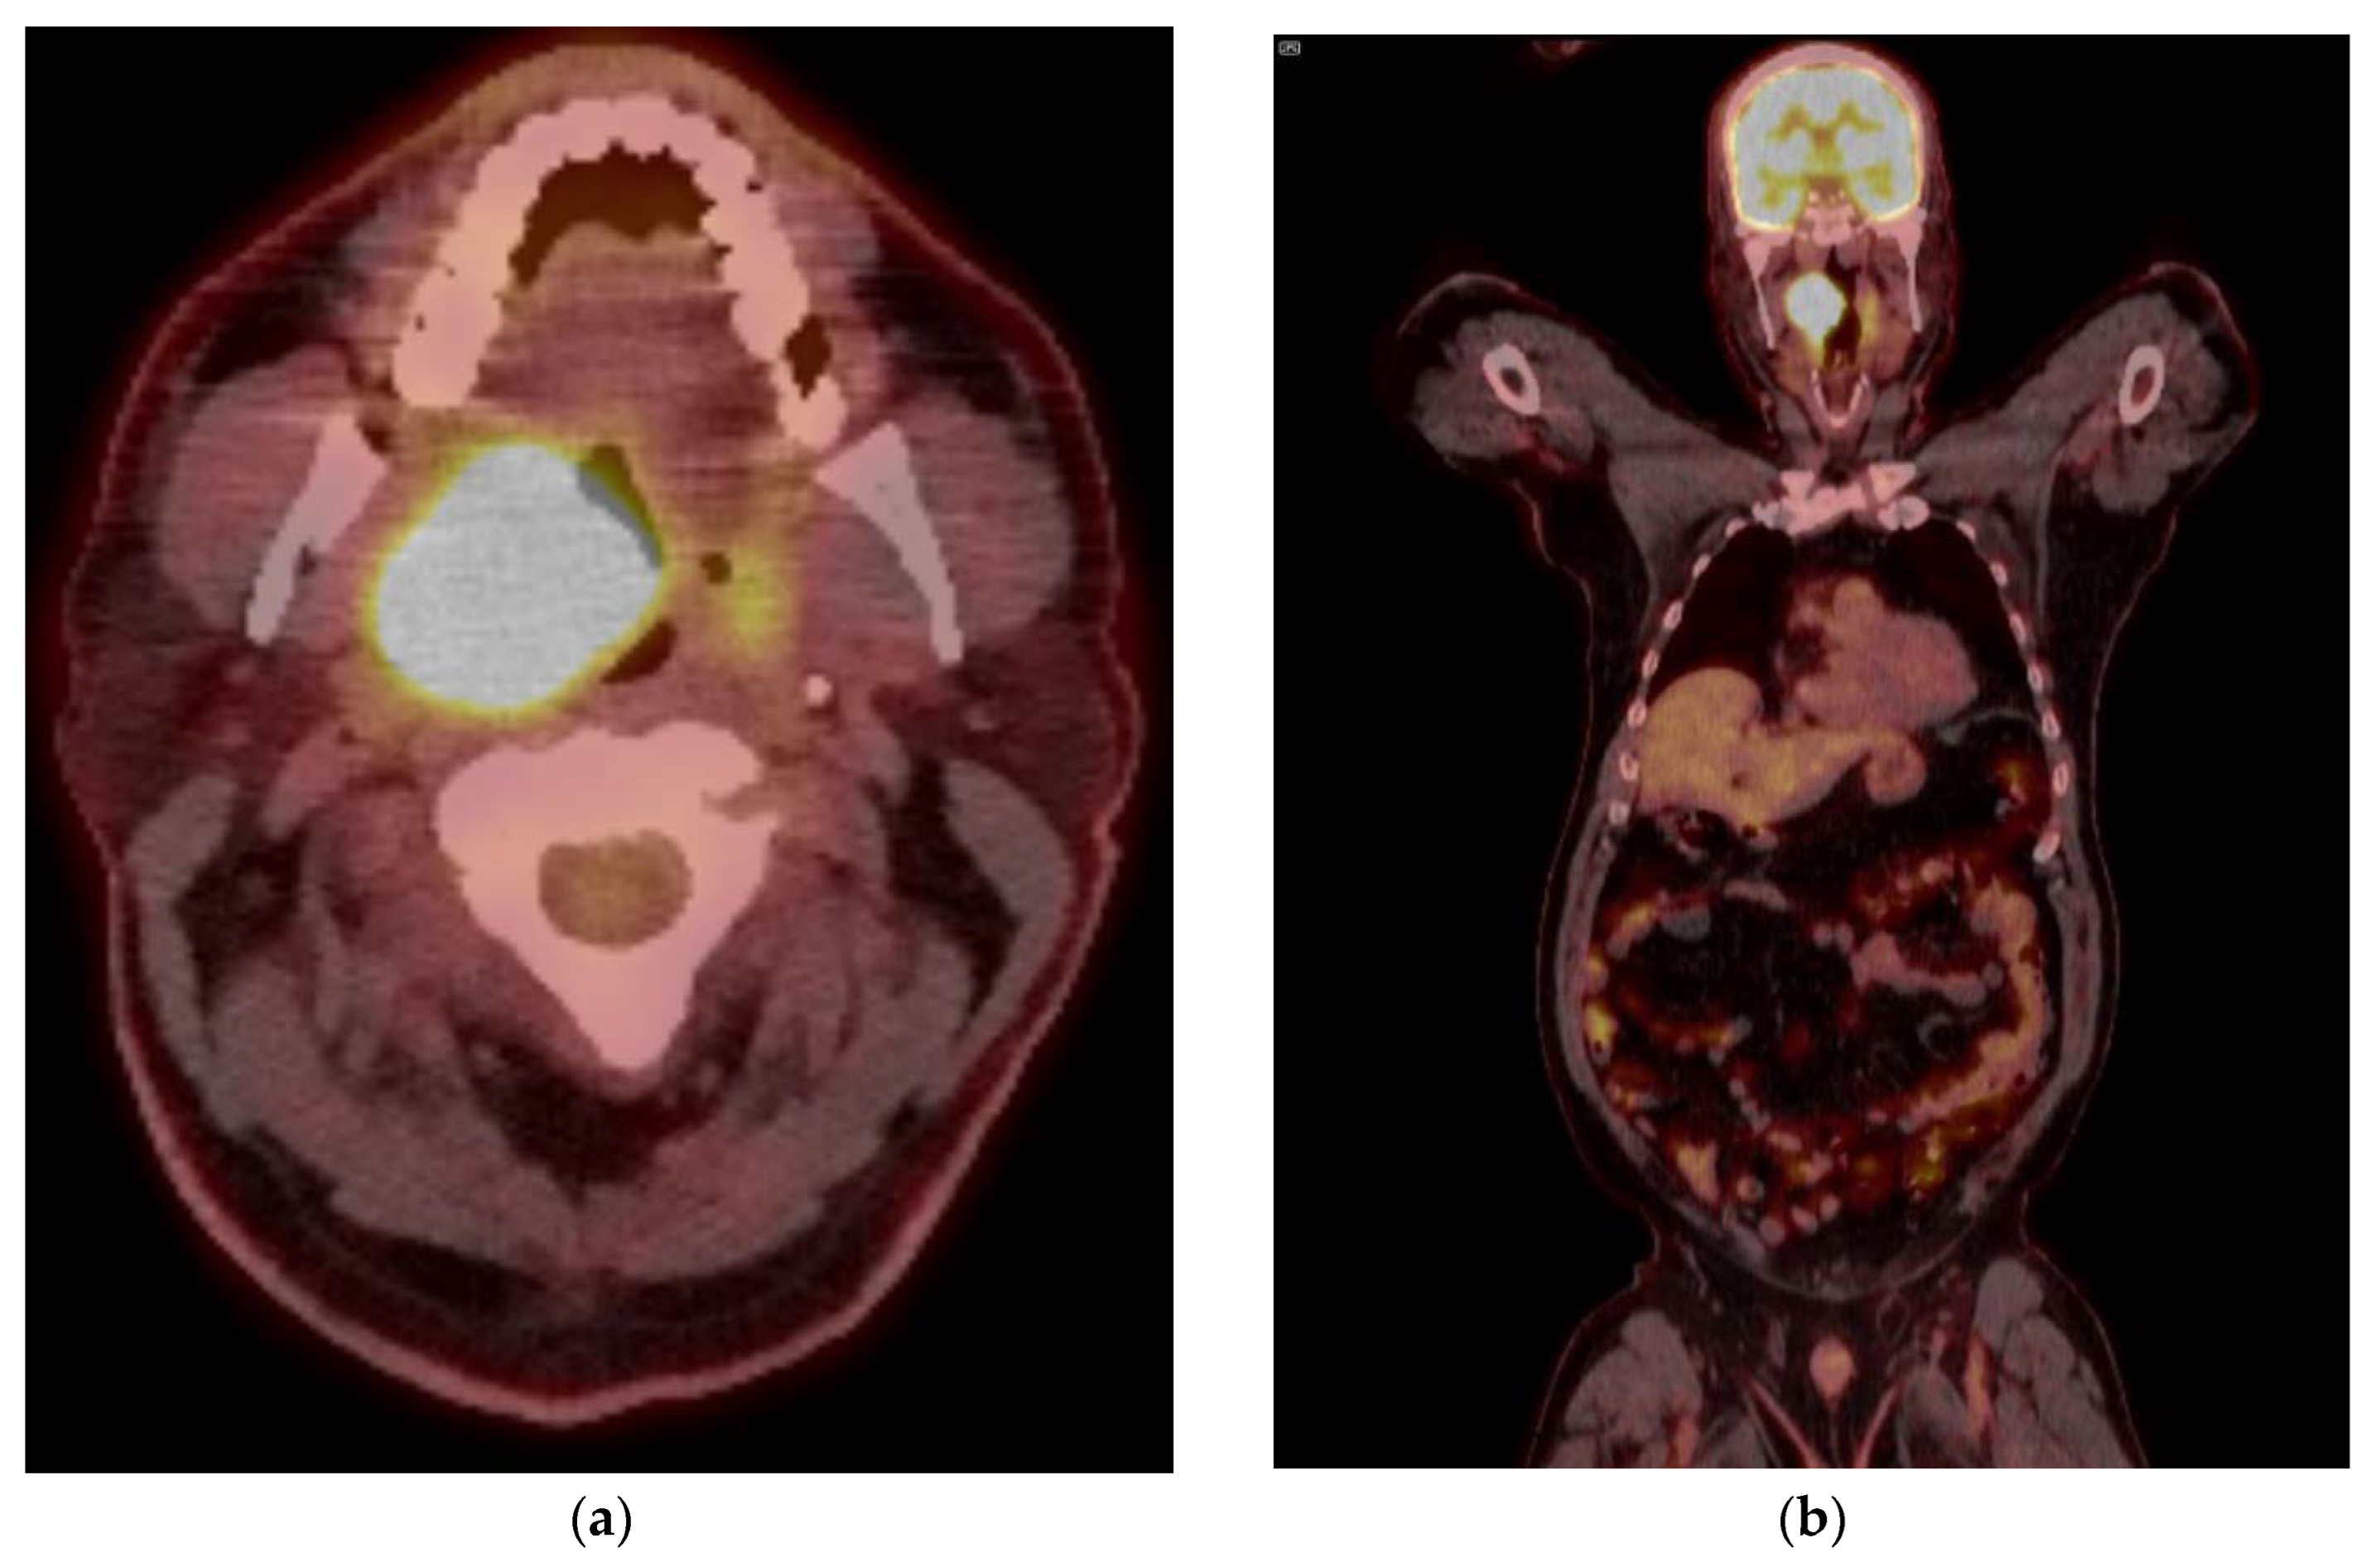

8.2. Response Assessment

- Gupta, T.; Master, Z.; Kannan, S.; Agarwal, J.P.; Ghsoh-Laskar, S.; Rangarajan, V.; Murthy, V.; Budrukkar, A. Diagnostic performance of post-treatment FDG PET or FDG PET/CT imaging in head and neck cancer: A systematic review and meta-analysis. Eur. J. Nucl. Med. Mol. Imaging 2011, 38, 2083–2095. [Google Scholar] [CrossRef]

- Mehanna, H.; Wong, W.L.; McConkey, C.C.; Rahman, J.K.; Robinson, M.; Hartley, A.G.; Nutting, C.; Powell, N.; Al-Booz, H.; Robinson, M.; et al. PET-CT Surveillance versus Neck Dissection in Advanced Head and Neck Cancer. N. Engl. J. Med. 2016, 374, 1444–1454. [Google Scholar] [CrossRef]